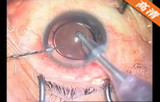

该手术在10点钟位透明角膜主切口制作,前房注入粘弹剂,2点钟位侧切口制作,撕囊镊做连续环形撕囊,做水分离和水分层 ,预吸晶状体皮质 ,超乳劈核法劈核,并逐块乳化吸除核块以及皮质,I/A吸除残留的皮质并对后囊膜进行抛光,前房及囊袋注入粘弹剂,植入爱尔康多焦人工晶状体,吸除前房以及人工晶状体后的粘弹剂。